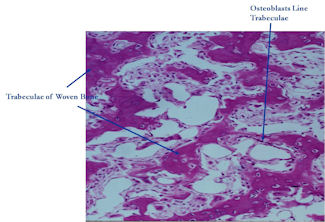

Microscopic Pathology

- Interlacing network of bone trabeculae in a loose fibrovascular stroma

- Prominent vessels

- Osteoblasts are plump, active, scattered mitotic figures

- Osteoblasts line up around periphery of trabeculae (Osteoblastic Rimming)

- Soft tissue component usually surrounded by shell of reactive bone or periosteum (Egg Shell Rim of Calcification)

- No cartilage production (as opposed to osteosarcomas that may contain areas of cartilage)